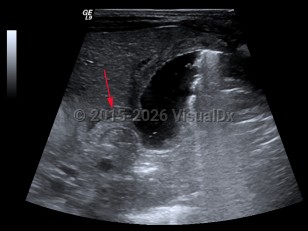

Hypertrophic pyloric stenosis

Hypertrophic pyloric stenosis (PS) is a narrowing of the pyloric lumen due to tissue hypertrophy and scarring. The resultant intestinal narrowing leads to gastric outlet obstruction and bowel obstruction. Although hypertrophic PS can very rarely occur in children and adults, this summary is focused on infantile hypertrophic PS. Patients present with emesis, usually within the first several months of life.

PS is predominantly seen in males (approximately 4:1) and presents typically at 2-7 weeks of life with nonbilious, postprandial projectile emesis and dehydration. Children of parents who had PS have a 20% increased risk of developing PS, suggesting a genetic component, although no clear genetic etiology has been identified.

PS is most common in people of Northern European descent, with an incidence range of approximately 2-5:1000 live births in these populations. PS is far less common in people of African and Asian descent. Prematurity, maternal smoking during gestation, and antibiotics within the first weeks of life are all independent risk factors for developing PS.

The complications of PS are due to dehydration and malnutrition. Patients often present with lethargy, failure to thrive, and a hypochloremic, hypokalemic metabolic alkalosis.

Symptoms will continue until a corrective pyloromyotomy is performed.